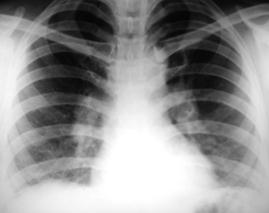

Рис. 4. Округлая тень